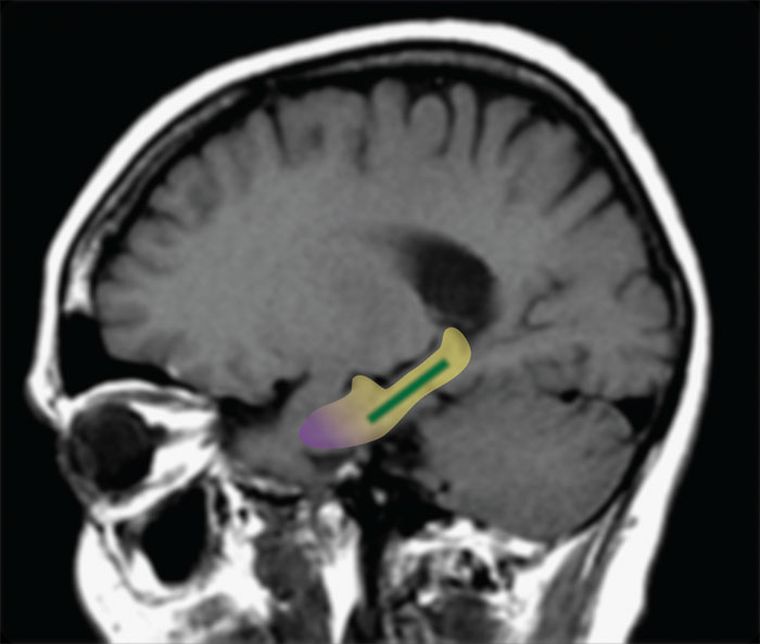

Los trabajos anteriores habían demostrado que los cambios en una parte específica del cerebro – el giro dentado – están asociados con la pérdida de la memoria relacionada con la edad. Hasta ahora, sin embargo, la evidencia en humanos sólo había mostrado un vínculo correlacional, no causal. Para ver si el giro dentado es la fuente de la pérdida de memoria relacionada con la edad en los seres humanos, el Dr. Scott A. Small y sus colegas probaron si los compuestos llamados flavonoles del cacao pueden mejorar la función de esa región del cerebro y mejorar la memoria. Anteriormente se había encontrado que los flavanoles extraídos del cacao pueden mejorar las conexiones neuronales en el giro dentado de los ratones.